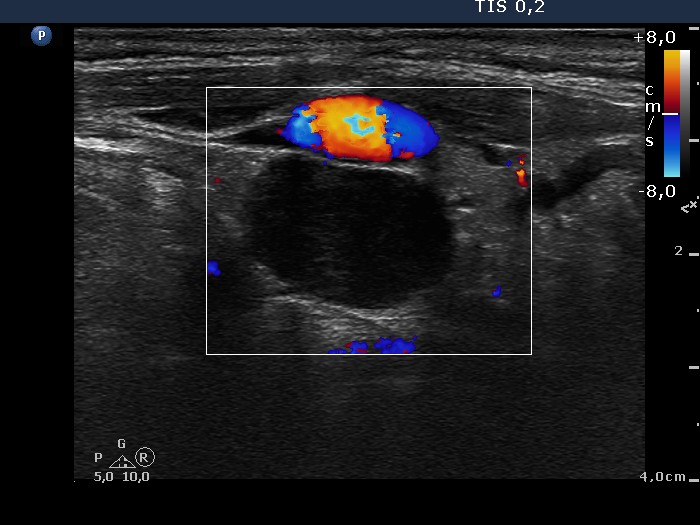

The echogenicity of the nodule - case 671 (ultrasonographic picture 6)

Left lobe, longitudinal view, color Doppler mode. The lesion is avascular.